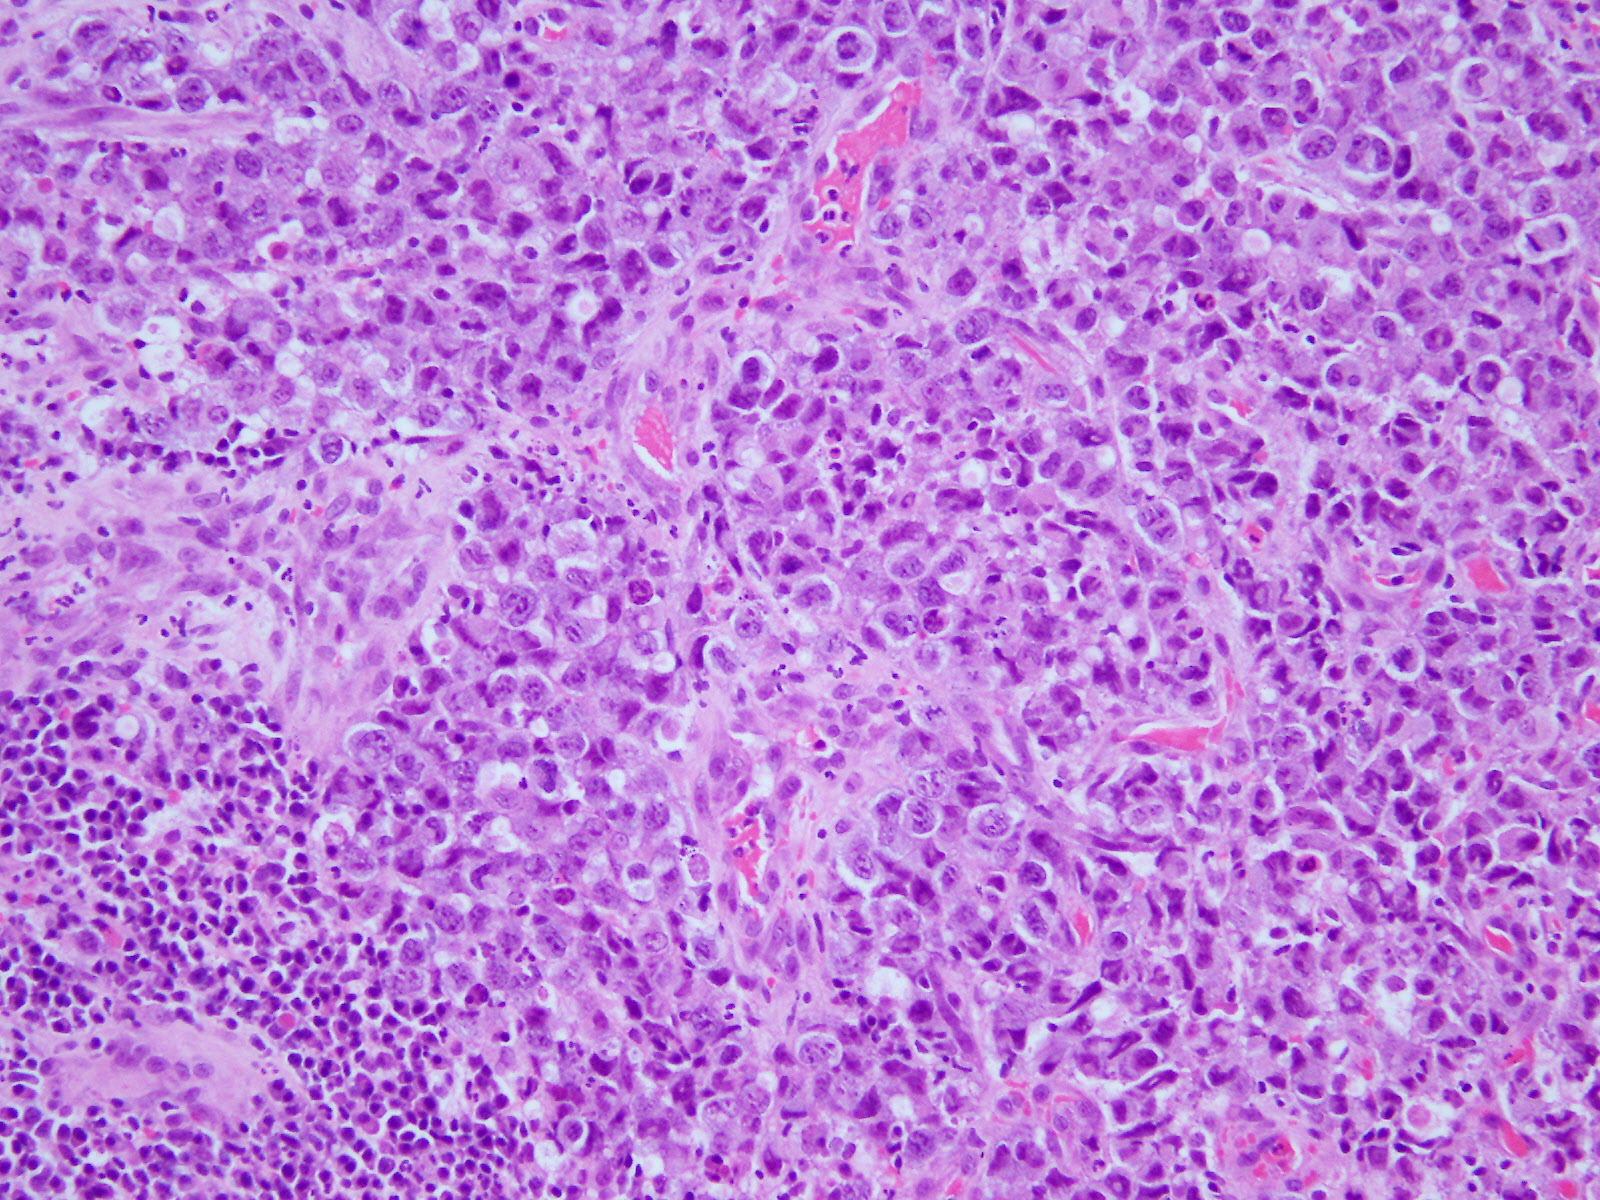

炎症性背景に、NC比増大、核形不整、核小体肥大を示す大型の細胞が弧在性に多数認められた。異型細胞は核異型が強く、一部、結合性を示すような細胞もみられた。

ギムザでは好塩基性を示す細胞や細胞質内空砲を認め、二核や馬蹄形核、ドーナツ状核を有する細胞も多くみられたことから、未分化大細胞型リンパ腫と診断した。(sIL-2Rは27598.1と高値)

未分化大細胞型リンパ腫は大型の細胞がみられ、核異型が強く、結合性を示すものもある。そのため、ホジキンリンパ腫や癌との鑑別を要する。

また、小リンパ球主体ではなく、異型の強い細胞が大半を占めていることからホジキンリンパ腫とも鑑別は可能である。

馬蹄形核、ドーナツ状核は未分化大細胞型リンパ腫の特徴的な細胞像であり、特徴を知っていれば診断可能な症例でもあるため今回症例提示した。